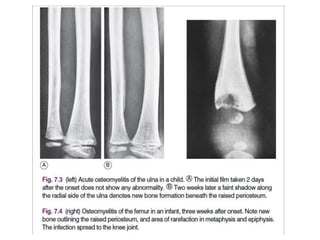

Pathology. Organisms reach the bone through the blood stream from a sep-

In the usual childhood manifestation, the infection begins in the metaphy-

bacterial growth (Fig. 7.1A); thence it may spread to involve a large part of the bone. The

subperiosteal abscess (Fig. 7.1B); later the abscess may burst into the soft tissues and may

X-Ray

• 1st 10 days Show No Abnormality .

Only after two or three weeks do visible changes appear, and they may never do

so if efficient treatment is started very early.

• By the end of the 2nd Week signs of rarefaction of Metaphysis and

New Bone Formation. Then sigs of healing

• Soft-tissue edema at 3-5 days after infection.

• Bony changes are not evident for 14-21 days:

– Early radiographic signs of rarefraction (thining of bony tissue

sufficient to cause decreased density of bone) of the

metaphysis and new bone formation outlining the raised

periosteum

– Sclerosis and thickening of the bone cortex at healing